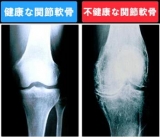

★関節の健康を守るためには★

健全な関節軟骨は、65~85%の水分とコラーゲンとプロテオグリカンという2種類の

たんぱく質を主成分としてスポンジ状のクッションを形成しています。

このプロテオグリカンの生成に欠かせないのがグルコミンサン・コラーゲンなのです。

関節の健康を守るために、積極的にグルコサミン・コンドロイチンを摂りましょう。

肘・膝・腰などの関節でクッションの働きをする軟骨を健康な状態に保つ大きな役割を

担うのがグルコサミン、コンドロイチン、コラーゲンです。

老化や過剰な運動などによってそれらを体内(軟化細胞)で合成する能力が、分解に比べて

相対的に低下します。

その結果、軟骨が変形したり摩擦をおこします。

そのため食べ物から摂る必要があるのです。